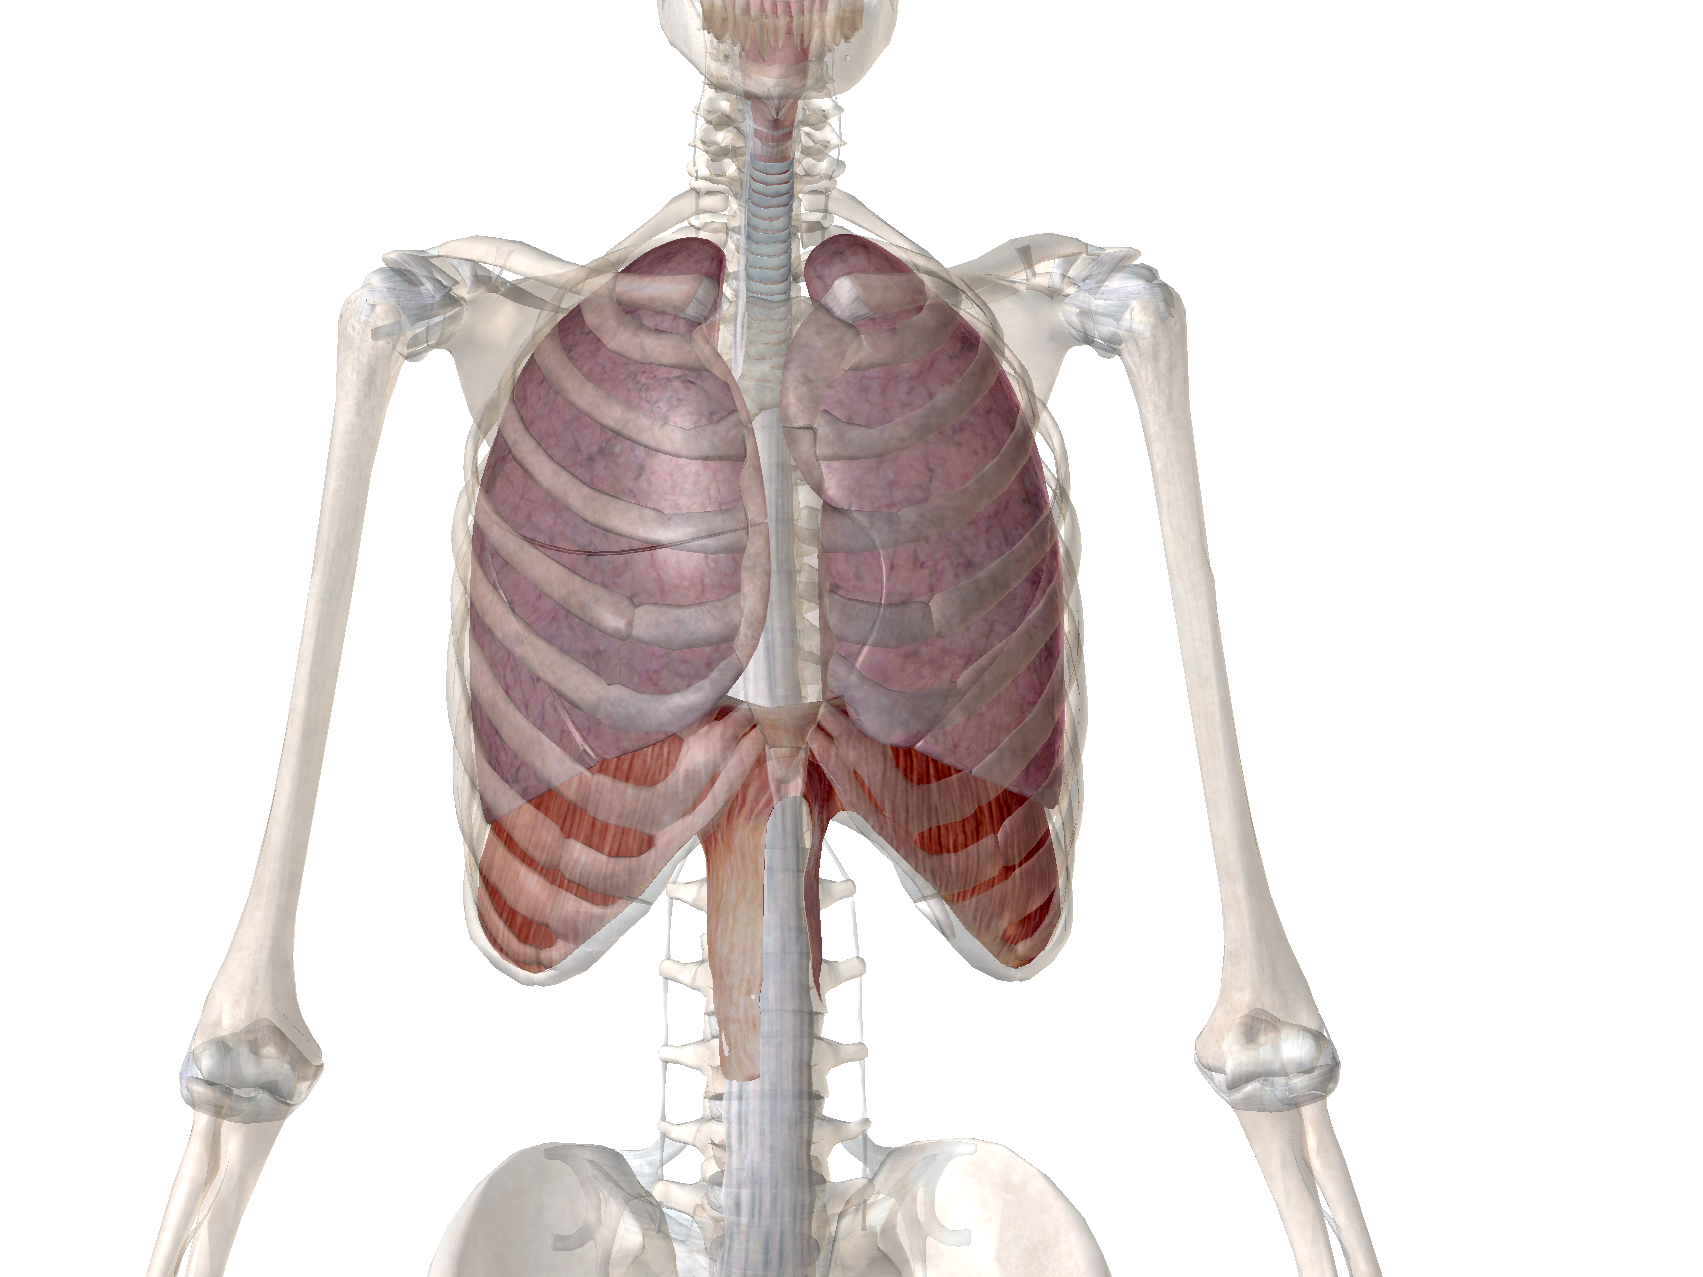

胸式呼吸

これです↓

こんな感じで、肋骨を拡げることでするのが「胸式呼吸」です。

対して腹式呼吸というのは

” 横隔膜を引きさげて “空気を取り込む呼吸法です。